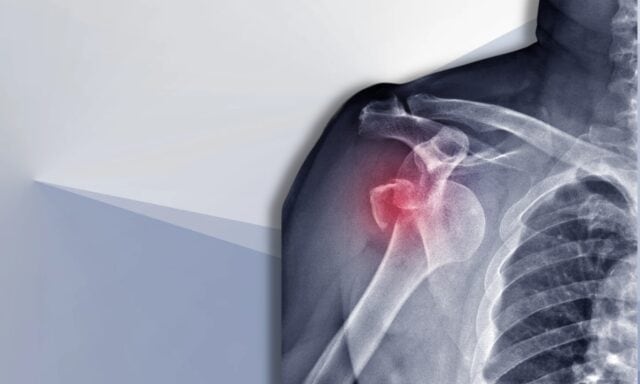

В этом эпизоде мы поговорим обо всем, что касается нестабильности плечевого сустава. Ты узнаешь больше о классификации Стэнмора и структурных повреждениях после вывихов. Мы обсудим типичного пациента с нестабильностью плечевого сустава и то, как выглядит процесс обследования. Мы коснемся паттернов активации мышц, хирургического вмешательства и того, как может выглядеть физиотерапевтическое ведение пациента с нестабильностью плечевого сустава. Так что обязательно послушай весь эпизод!